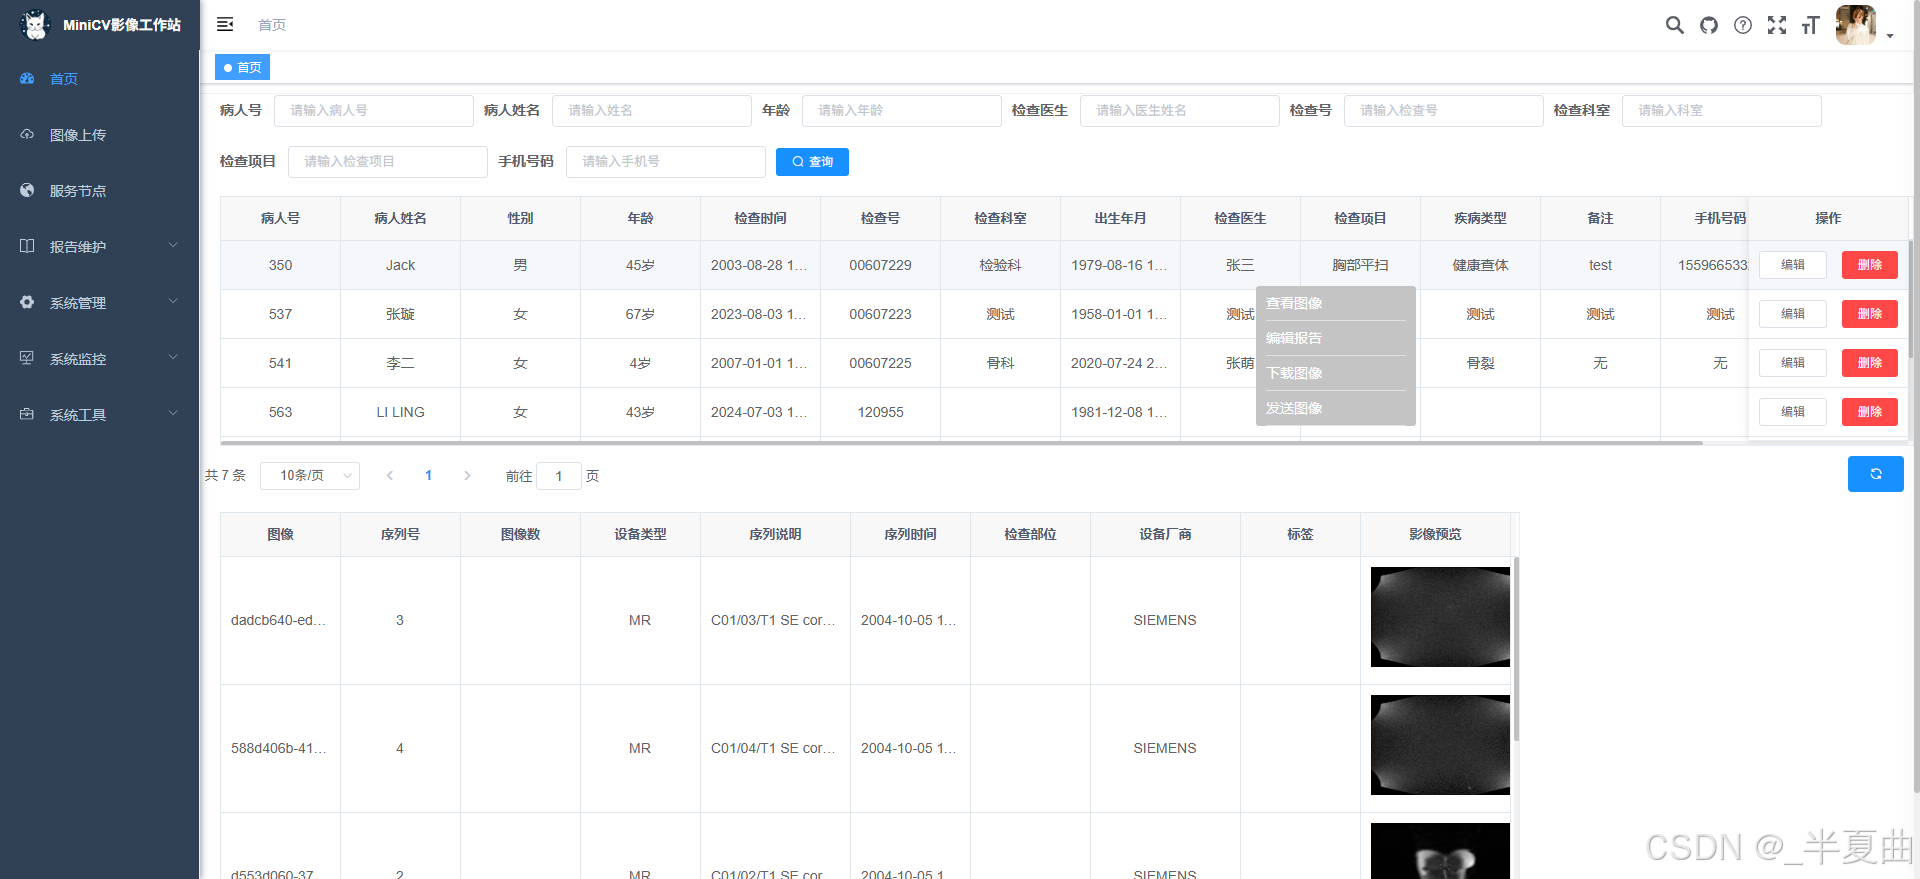

患者检查列表展示及维护功能;

检查下序列影像的列表(单帧影像预览)功能;

患者检查首页-展示: